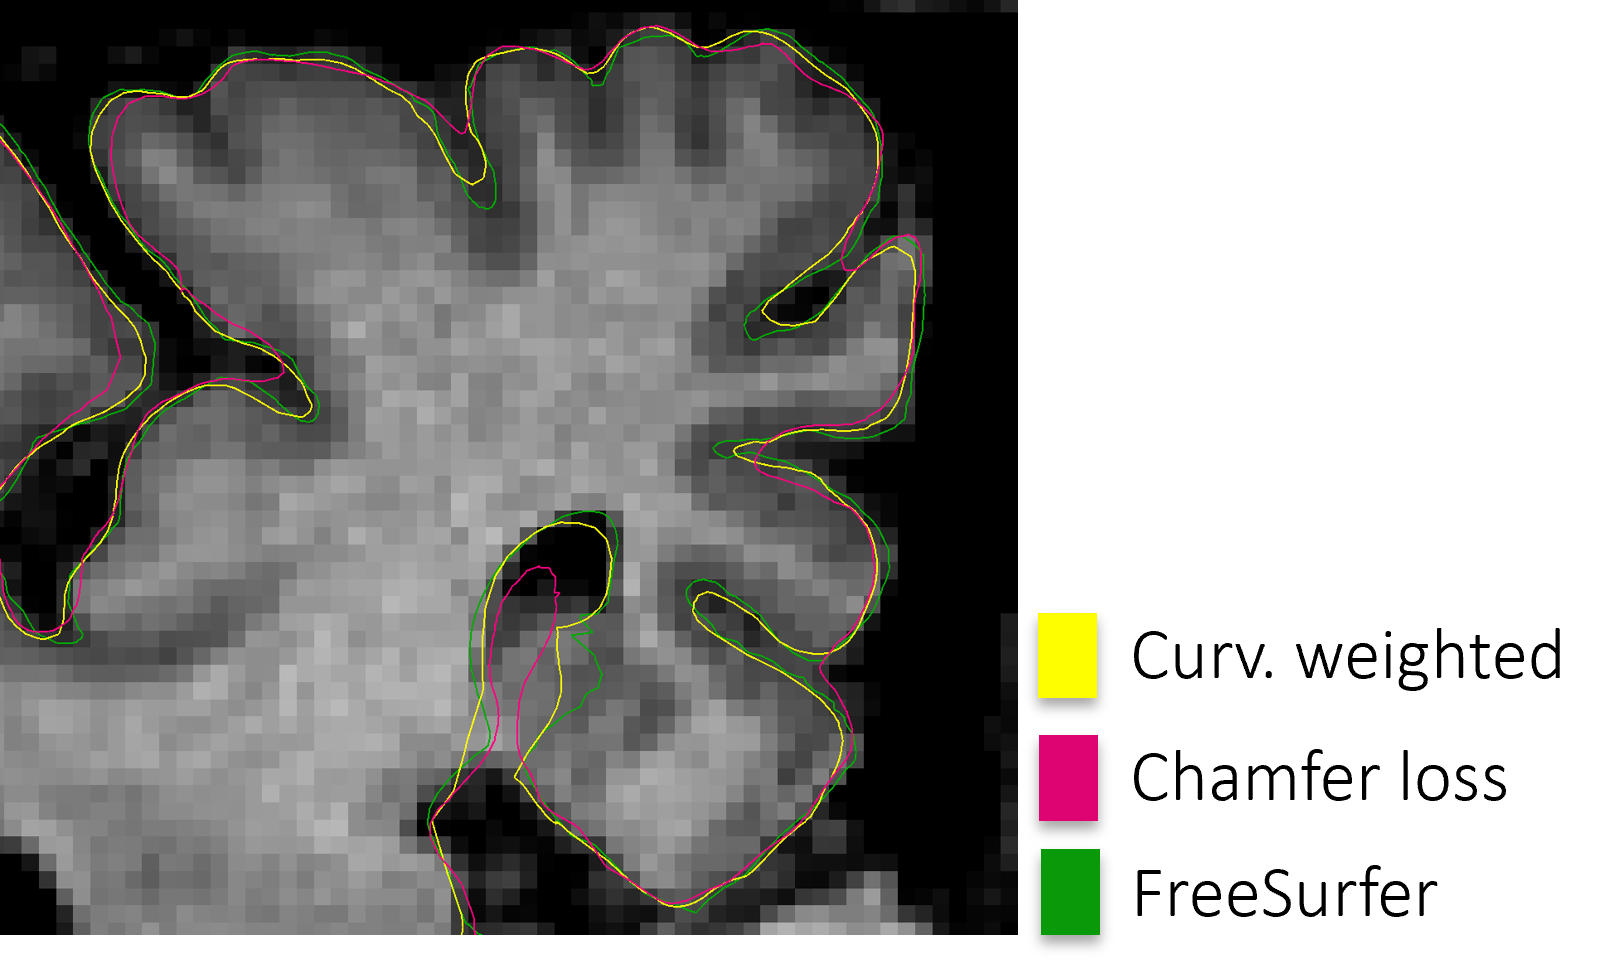

This article substantially extends our previous work on cortical surface reconstruction [2] by introducing, for the first time, numerically integrable graph deformation blocks (graph NODEs). This reduces the number of network parameters without losing any expressiveness. Moreover, we improve the results and include a large variety of new experiments. More precisely, we (i) initialize the surface reconstruction with FreeSurfer’s fsaverage and population-specific reference templates, which allows us to (ii) solve cortex parcellation as an additional task at minimal extra cost. Further, we (iii) assess the geometric consistency of reconstructed points learned with the curvature-weighted Chamfer loss, which challenges the common approach of separating the cortex segmentation from the registration. Finally, we (iv) include four more recent baselines and (v) report results on three new datasets with varying scanner types, demographics, diagnoses, and manually set landmark points.

We leverage the curvature-weighted Chamfer distance CwCsubscriptCwC\mathcal{L}_{\text{CwC}} introduced in [2] to assure geometric accuracy. In addition, we train with two regularizing terms: the edge loss edgesubscriptedge\mathcal{L}_{\text{edge}} and the (intra-mesh) normal consistency loss NCsubscriptNC\mathcal{L}_{\text{NC}}. Intuitively, the regularizers enforce the regularity and smoothness of the output surfaces. In summary, the mesh loss is defined as

Curvature-weighted Chamfer loss. A major challenge in deformation-based surface reconstruction methods is to set the ratio between accuracy and regularization terms in the loss function. This is, in particular, challenging in the brain as the regularization could easily lead to a deficit in accuracy in highly curved regions (cf. Supplementary Figure 1). To address this issue, we leverage the curvature-weighted Chamfer loss [2], which re-weights the ratio between point and regularization losses locally based on ground-truth curvature. It gives higher importance to the point loss in highly curved regions and it is defined as

CwC(p,gt)=1|𝒬gt|u𝒬gtκ(u)minv𝒬puv2+1|𝒬p|v𝒬pκ(u~)minu𝒬gtvu2,subscriptCwCsuperscriptpsuperscriptgt1superscript𝒬gtsubscriptusuperscript𝒬gt𝜅uvsuperscript𝒬psuperscriptdelimited-∥∥uv21superscript𝒬psubscriptvsuperscript𝒬p𝜅~uusuperscript𝒬gtsuperscriptdelimited-∥∥vu2\begin{split}\mathcal{L}_{\text{CwC}}({\mathcal{M}}^{\mathrm{p}},{\mathcal{M}}^{\mathrm{gt}})&=\frac{1}{\lvert{\mathcal{Q}}^{\mathrm{gt}}\rvert}\sum_{\text{u}\in{\mathcal{Q}}^{\mathrm{gt}}}\kappa(\text{u})\underset{\text{v}\in{\mathcal{Q}}^{\mathrm{p}}}{\min}\lVert\text{u}-\text{v}\rVert^{2}\\ &+\frac{1}{\lvert{\mathcal{Q}}^{\mathrm{p}}\rvert}\sum_{\text{v}\in{\mathcal{Q}}^{\mathrm{p}}}\kappa(\tilde{\text{u}})\underset{\text{u}\in{\mathcal{Q}}^{\mathrm{gt}}}{\min}\lVert\text{v}-\text{u}\rVert^{2},\end{split} (7)

where u~=argminr𝒬gtvr2\tilde{\text{u}}=\operatorname*{arg\,min}_{\text{r}\in{\mathcal{Q}}^{\mathrm{gt}}}\lVert\text{v}-\text{r}\rVert^{2}. 𝒬p={qiqip1iN}superscript𝒬pconditional-setsubscript𝑞𝑖subscript𝑞𝑖superscriptp1𝑖𝑁{\mathcal{Q}}^{\mathrm{p}}=\{q_{i}\mid q_{i}\in{\mathcal{M}}^{\mathrm{p}}\wedge 1\leq i\leq N\} and 𝒬gt={qiqigt1iN}superscript𝒬gtconditional-setsubscript𝑞𝑖subscript𝑞𝑖superscriptgt1𝑖𝑁{\mathcal{Q}}^{\mathrm{gt}}=\{q_{i}\mid q_{i}\in{\mathcal{M}}^{\mathrm{gt}}\wedge 1\leq i\leq N\} are N=50,000𝑁50000N=50,000 predicted and ground-truth points, respectively, sampled from the surfaces in a differentiable manner [14, 57]. κ(p)[1,κmax]𝜅p1subscript𝜅\kappa(\text{p})\in\left[1,\kappa_{\max}\right] is a point weight based on the local discrete mean curvature [39]. We set κmax=5subscript𝜅5\kappa_{\max}=5 as in [2].

In comparison to other DL-based methods for cortical surface reconstruction, V2C-Flow performs comparable to the best alternative methods, i.e., CorticalFlow++ (CF++) and CortexODE (CODE), with V2C-Flow being in the forefront on both, WM and pial, surfaces. We attribute the highest accuracy of CF++, CODE, and V2C-Flow to the continuous-time deformation process that they have in common. In terms of training time, though, V2C-Flow is about 10 times faster than CF++, taking three days instead of four weeks. The long training time in CF++ is probably due to the compute-intensive ODE-solver (Runge-Kutta method with 30 integration steps) and the separate modeling of the deformation fields (three UNets per surface). CODE, on the other hand, is slower in terms of inference time (14s vs. 1.6s in V2C-Flow, cf. fig. 3) due to the sequential segmentation and mesh extraction approach and does not come with point correspondences to a template. Other DL-based baseline methods, either template-based (Vox2Cortex [2] (V2C), CorticalFlow [29] (CF), TopoFit [21]) or SDF-based (DeepCSR [50]), are clearly outperformed in terms of surface accuracy. Supported by the observations from Figure 3 and Supplementary Table 2, we further argue that the separate modeling of surfaces in CF/CF++ and TopoFit bears the risk of creating many anatomically implausible intersections between WM and pial surfaces. Instead, the joint modeling in V2C-Flow reduces the number of intersecting WM and pial surfaces. Further artifacts of existing methods like intersections with the skull (CF, CF++) and distorted surfaces (DeepCSR, FreeSurfer) are also alleviated in V2C-Flow as shown in Figure 3.

In Figure 4, we compare the generalization ability of V2C-Flow to results obtained in a similar setup with CorticalFlow (CF) [29], and CorticalFlow++ (CF++[51]. CF and V2C-Flow are implemented to be aptly comparable, using the same template, UNet architecture, and optimizer (cf. implementation details in Supplementary Material). CF++ uses a larger template and higher-order ODE solver, which is currently not applicable to V2C-Flow due to training memory and time limitations, but we include it nonetheless as the state-of-the-art baseline. Quantitatively, we illustrate the distribution of HD90 distances for the three methods in different evaluation scenarios. In addition, we depict exemplary MRI slices with pial boundaries from all methods. Again, we use data from J-ADNI, OASIS, and Mindboggle. However, this time we consider the individual substudies from Mindboggle separately, namely HLN, MMRR, NKI-RS, and NKI-TRT. As a reference, we plot the distribution of surface distances on the ADNI test set, which corresponds to an internal evaluation. The remaining plots show the performance using the external datasets. We find that V2C-Flow yields higher accuracy than CF on all external test sets and outperforms CF++ on MMRR and NKI data. Remarkably, these are also the scans that differ most significantly from the ADNI scans in terms of brightness and contrast. The zoomed-in regions in Figure 4 indicate high accuracy of V2C-Flow in tightly folded regions with fewer vertices than CF++. This is rendered possible by the special emphasis on these regions in our curvature-weighted Chamfer loss.

We have introduced Vox2Cortex-Flow (V2C-Flow), a novel end-to-end deep learning method for cortical surface reconstruction that maintains vertex-wise correspondences to an input template. To this end, a continuous neural mesh-deformation scheme based on stacked graph NODEs and conditioned on deep image features is proposed. Our extensive experiments on internal and external neuroimaging data show that V2C-Flow reconstructs all four cortical surfaces simultaneously within less than two seconds on a standard GPU, yields state-of-the-art surface accuracy, and avoids topological errors in related methods. Moreover, we find that the consistency of reconstructed points, learned by our curvature-weighted Chamfer loss, and accompanied cortical thickness measurements are surprisingly higher than in the spherical-registration-based baseline. This observation challenges the common approach of segmentation-based methods that separate surface extraction from the registration. Instead, we suggest a consolidated approach that combines segmentation, topology correction, surface extraction, inflation, registration, and resampling into a single forward pass of our geometric neural network.